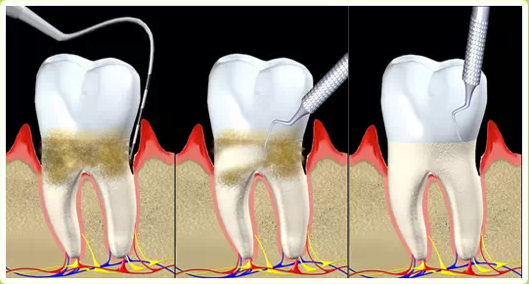

Toothbrushing is indeed the foundation of daily oral care, but its effectiveness is far from perfect . Even with diligent daily brushing, most people are unable to completely control the formation of dental plaque . Dental plaque is a biofilm composed of bacteria, food debris, and saliva that continuously reforms on the tooth surfaces . It particularly thrives in areas difficult to reach by toothbrushes, such as between the teeth (interproximal areas) and within the gingival sulcus .

Professional teeth cleaning, medically referred to as "supragingival scaling" , is the process of using specialized instruments to remove supragingival calculus (tartar), plaque, and stains from the teeth . Unlike daily brushing, professional cleaning can access and thoroughly clean areas that toothbrushes cannot effectively reach, such as the gumline and deep between the teeth, effectively removing established calculus and tenacious plaque deposits .

Thorough Removal of Plaque and Calculus: Addresses deep cleaning issues that brushing cannot handle, eliminating the primary cause of periodontal diseases .